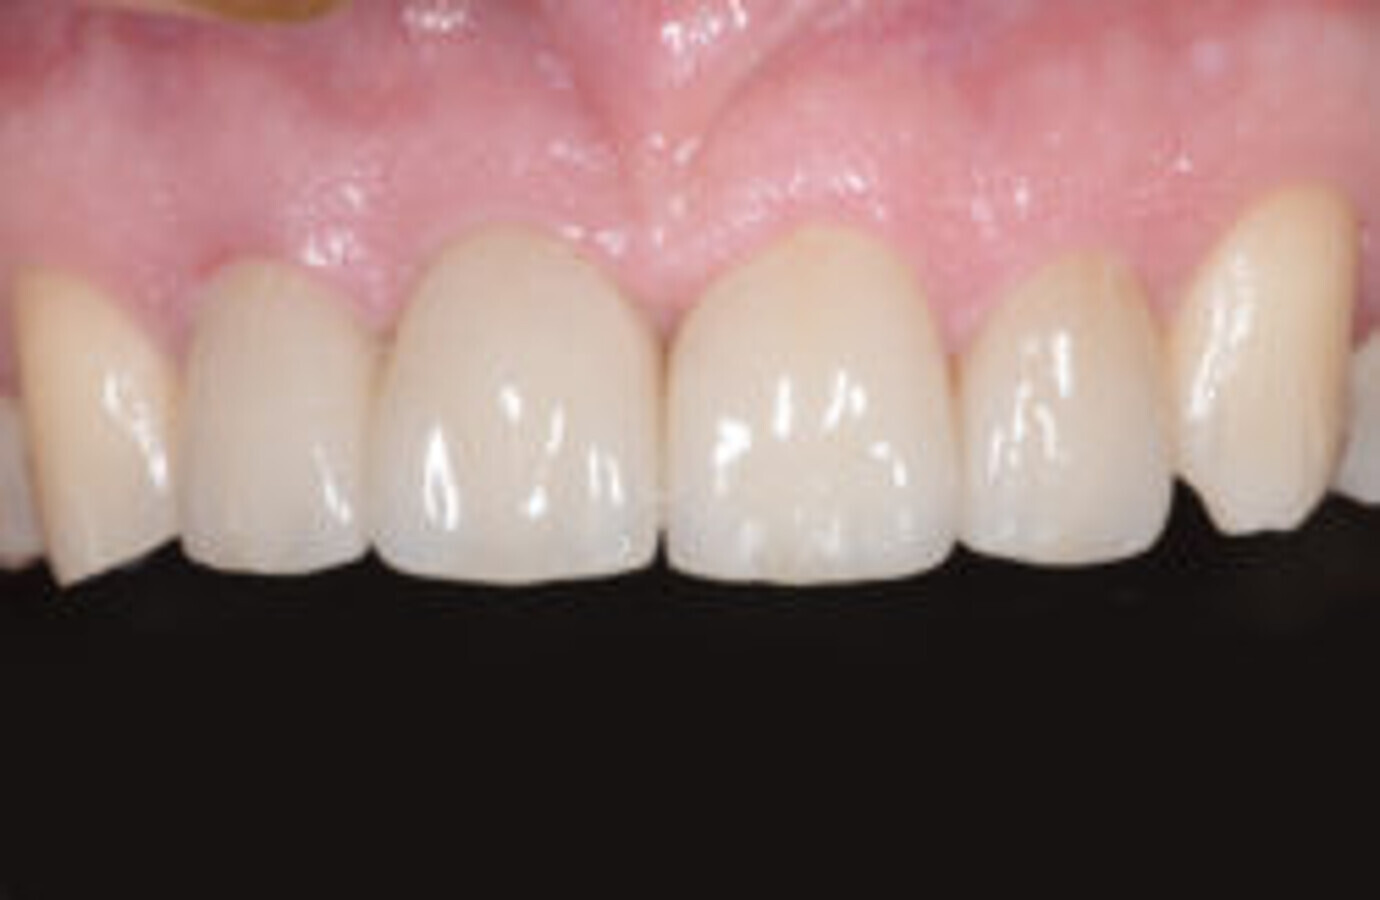

图18. 种植体周围的软组织适应良好。此外,在#12(根管治疗后)安装了陶瓷冠,#21和#22安装了陶瓷贴面。三年的随访显示软、硬组织无殊。

治疗非常成功,最终结果患者十分满意。三年后复诊可见种植体周软组织适应性良好(图18)。此外,#12根管治疗后安装了陶瓷冠,#21和#22安装了陶瓷贴面。